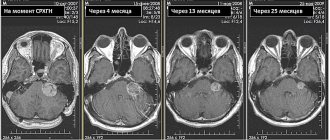

Аденома гипофиза головного мозга (АГГМ) представляет собой опухоль железистой ткани мозгового придатка. Гипофиз –

Общие сведения о патологии Заболевание: встречается нечасто; протекает медленно; редко переходит в злокачественную форму;